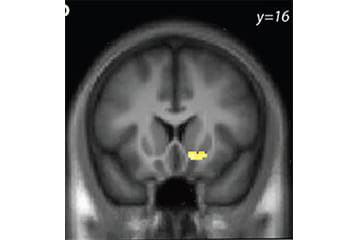

image of a brain scan

fMRI Study of Working for Alcohol

In addition to an in-person screening, this study requires an overnight stay at University Hospital’s Clinical Research Center in Indianapolis. On the first day, participants briefly experience intravenously administered alcohol and have an MRI at Goodman Hall while they perform a task. Depending on task performance, participants may then have the opportunity to administer themselves intravenous alcohol following the MRI scan. Participants then spend the night at University Hospital and are discharged at 10:30 am the following day. This study is conducted primarily on Tuesdays, Wednesdays and Thursdays. Participants in this study receive up to $575 and have the opportunity for additional payment during the study visit.